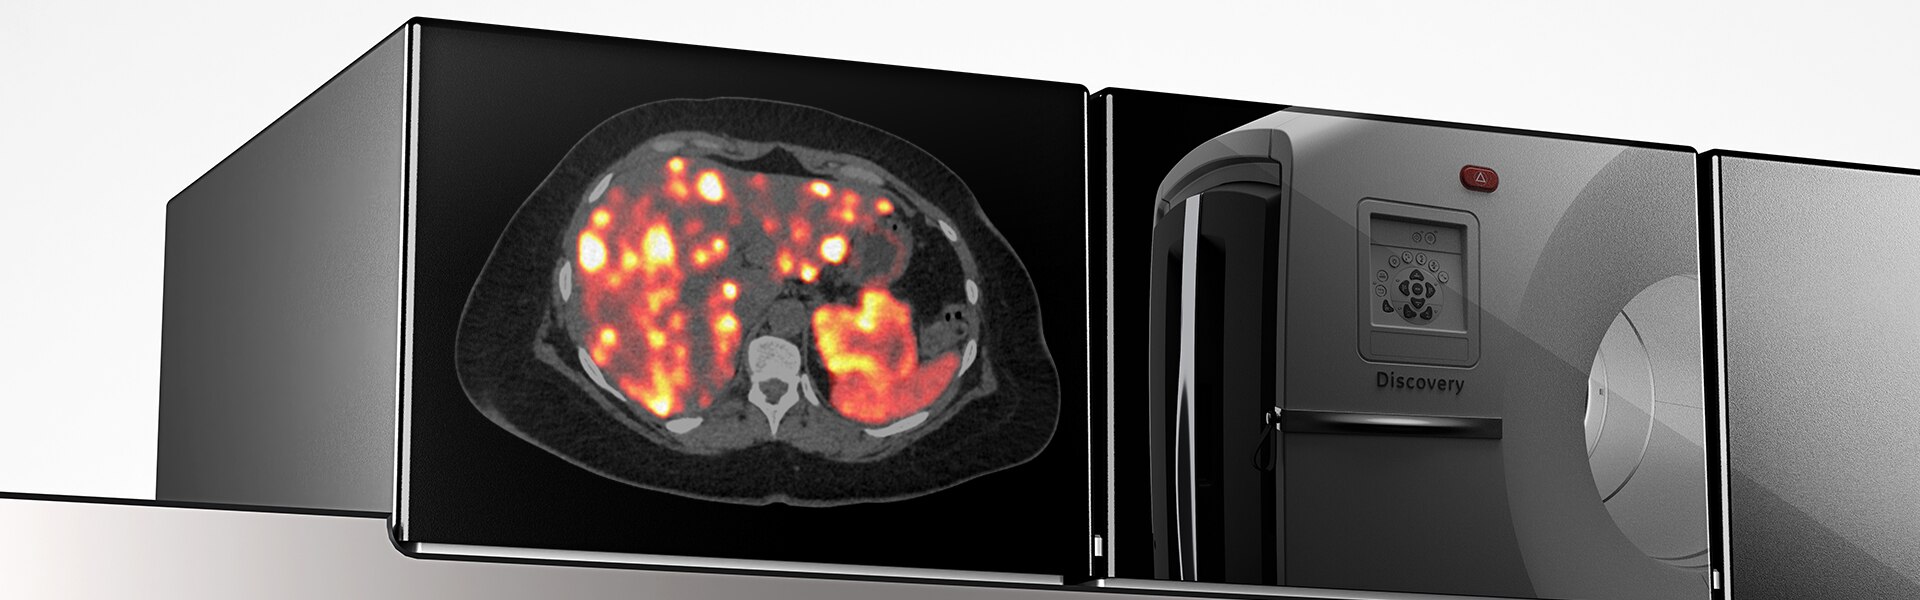

Digital algılamada yeni dönem

Discovery MI Gen 2, çözüm sunmak üzere tasarlanmıştır

- Ölçeklendirilebilir görüntüleme alanı

- NECR'de yüzde 50'lık artış

- cm başına sıra dışı hassasiyet (cps/kBq/cm)

- Tarama süresinde yüzde 33 azalma

- Verilen dozda yüzde 33 azalma

Yeni nesil dijital PET